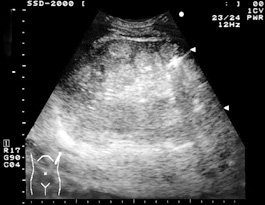

![]() 脾実質内に直径2〜3cm大のややエコーレベルの高い腫瘤が,密集して描出されている. |